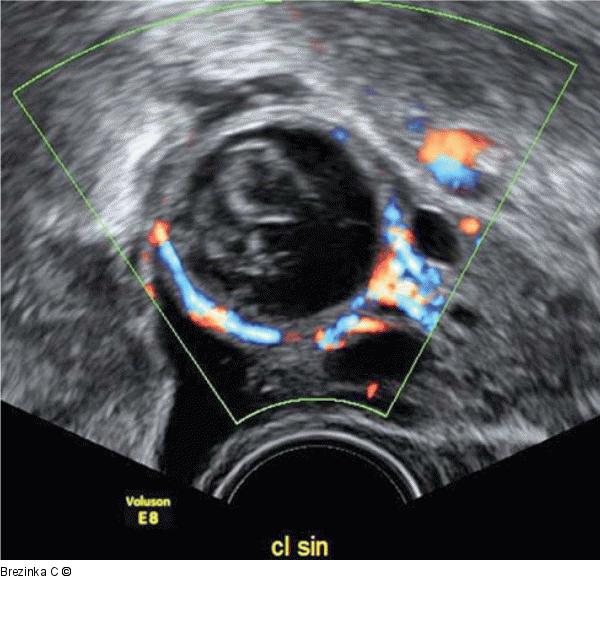

Abbildung 2: Gyn-Ultraschall Dieses Corpus luteum hat eine große „central fluid-filled cavity“ mit irregulären Koageln im Inneren. |